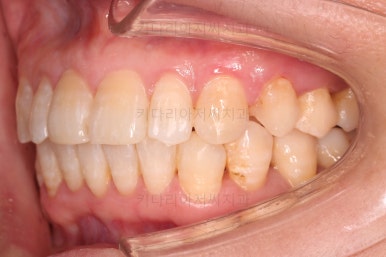

초진 시, 입안의 모습이에요.

"최근 들어 점점 틀어지고, 점점 튀어나오고, 점점 사이가 벌어져요."

성장이 끝난 성인들은 해가 갈수록 특히 아래앞니가 삐뚤어지는 것은 자연스러운데요.

이번 환자분의 말씀대로 최근에 변하가 심하게 나타난 경우는 원인이 딱 하나에요.

잇몸(치주)

흔히 풍치라고 하죠.

전반적인 잇몸이 나빠진다 -> 어금니가 씹는 힘에 버텨주지 못하고 앞으로 쓰러진다. -> 앞니가 강하게 부딪히며 아래앞니가 윗니를 앞으로 쳐낸다. -> 돌출입이 생기고, 앞니 사이 틈새가 생긴다.

앞니가 튀어나오고 틈새가 생기는 것이 결과이긴 하지만 원인은 어금니쪽 잇몸에서부터 찾아야해요.